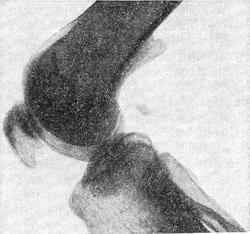

![]() Экзостоз задньої поверхні стегнової кістки (рентгенограма).  |

Екзостоз - це доброякісні шиповидні кістково-хрящові утворення на поверхні кістки (рис.). Бувають поодинокі або множинні, мають форму шипа, гриба, цвітної капусти та ін Етіологія екзостозів - дисплазія зон росту. Захворювання нерідко носить сімейний спадковий характер.

Екзостоз виявляються, як правило, в дитячому та юнацькому віці. Поодинокі екзостоз частіше утворюються в дистальному метафизе стегна, проксимальному метафизе великогомілкової кістки, рідше на верхній кінцівці. Множинні екзостоз (іноді до декількох десятків) локалізуються симетрично в області метафизов довгих трубчастих кісток, ребер, ключиці.